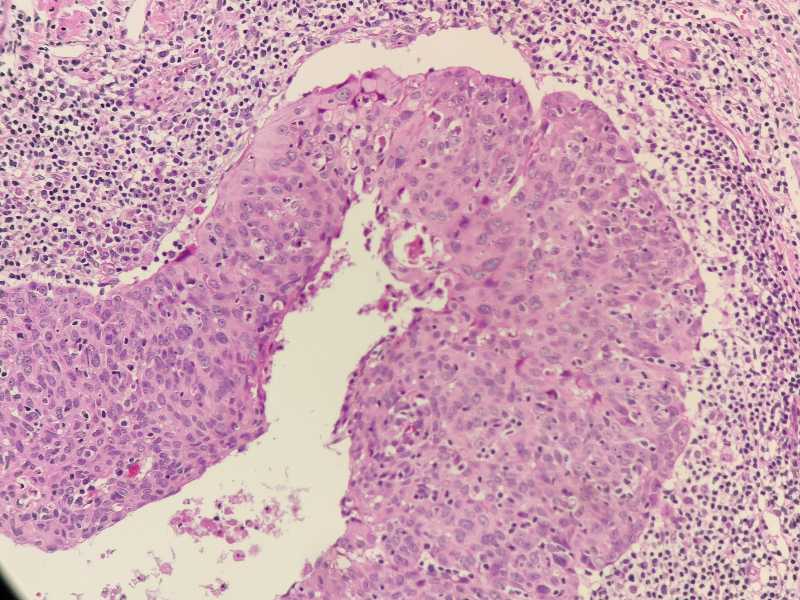

女40岁宫颈锥切组织浸润还是CIN累腺

女40岁宫颈锥切组织 浸润还是CIN累腺?

考虑:鳞癌